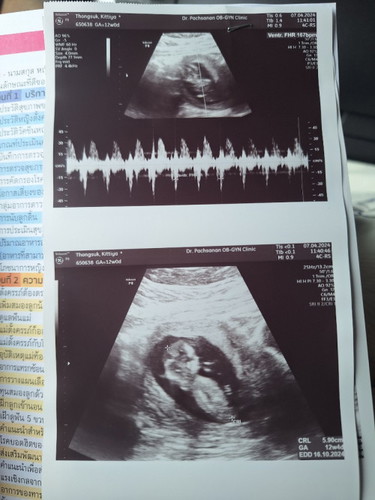

กำหนดคลอดในใบอัลตร้าซาวด์

สอบถามแม่ๆคะ เชื่อกำหนดคลอดซาวตอนแรกๆเลยคือ6-7w หรือเชื่อตอน10-13w คะเพราะกำหนดคลอดเคลื่อนคะ รอบแรก20ตค. รอบ2 13 ตค คะ

หมอที่เราฝากครรภ์แจ้งว่า ห่างกันไม่เกิน10 วัน ก็ไม่ต้องสนใจตรงนี้ค่ะ เอาที่หมอบอก ไม่ต้องดูจากใบอัลตร้าซาวน์ ดูจากการมีประจำเดือนวันแรกของรอบล่าสุด